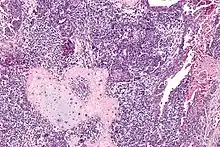

Carcinosarome utérin. HE, x250

Invasion du myomètre par un carcinosarcome utérin avec différenciation rhabdomyosarcomateuse. HE, x400